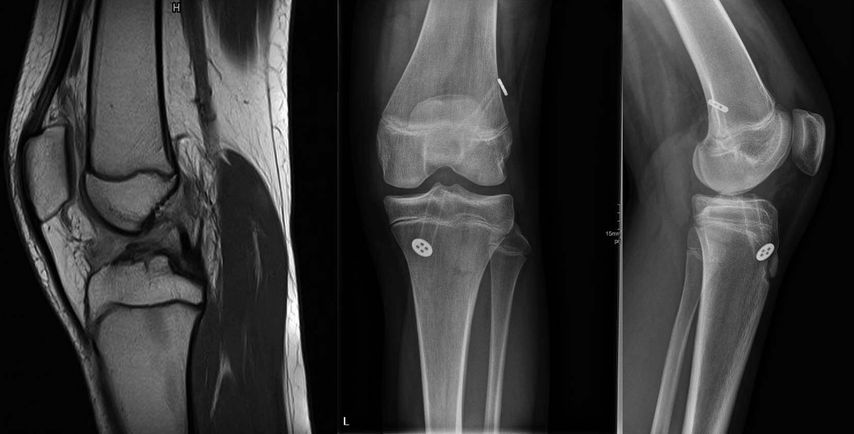

Bei den fugenkreuzenden Techniken können beide oder nur ein Kanal transepiphysär angelegt werden. Eine Verletzung der Tuberositas tibiae soll jedenfalls vermieden werden und die Epiphysenfugen sollten nicht mit Knochenblöcken oder Implantaten überbrückt werden. Bei jugendlichen Patienten kurz vor dem Wachstumsabschluss stellt die transepiphysäre VKB-Rekonstruktion ein reproduzierbares und verlässliches Verfahren dar (Abb. 3).

Abb. 3: MRT einer 13-jährigen Fußballerin mit VKB-Ruptur und postoperative Röntgenbilder nach Rekonstruktion mit autologer 4-fach-Semitendinosussehne und extrakortikaler Fixation (aus Reuter und Stotter 2022)45